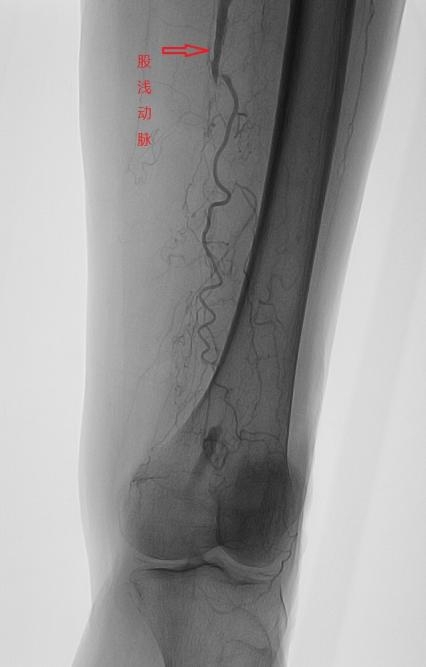

2025-03-18痛则不通……脚痛,有可能是这里“塞”了

脚痛,这一普遍存在的身体信号,其背后的成因多种多样,涵盖了从炎症、外伤、痛风到糖尿病足等一系列健康问题。然而,让人意想不到的是,下肢动脉硬化闭塞症这一血管疾病,也可能会以脚痛的形…